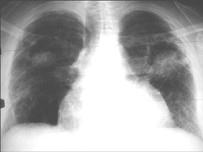

问题 男,48岁,发热,咳嗽,咳痰,咯血,PPD(-),请结合图,最可能的诊断是 ( )

选项 A.肺癌 B.肺曲菌病 C.肺结核 D.肺炎 E.肺脓肿

答案 B